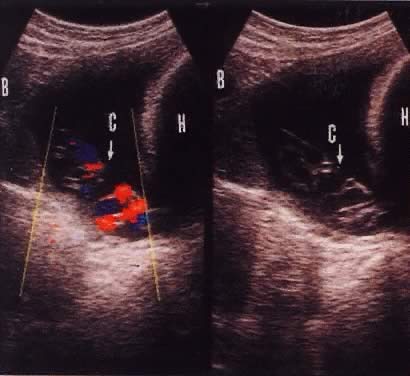

Funic presentation before rupture of membranes is a predisposing factor to umbilical code prolapse. This is visualized on ultrasound in approximately 1 in 167 (0.6%) live births.16 The increased use of antepartum obstetric ultrasound, especially with color flow Doppler, has assisted in making the diagnosis of a presenting cord and preparing for cesarean delivery before overt or occult prolapse. Figure 2 illustrates the usefulness of color flow Doppler in this diagnosis. Every patient with fetal malpresentation, multiple gestation, or known abnormal placentation should undergo ultrasound examination before labor to exclude the possibility of funic presentation. Ultrasound also can be helpful for the preterm fetus in assessing the contents of hour-glassing membranes.

Fig. 2. Color flow Doppler and gray-scale images of funic presentation.(Raga F, Osborn N, Ballester MJ et al: Color flow Doppler: A useful instrument in the diagnosis of funic presentation. J Natl Med Assoc 88:94, 1996.)